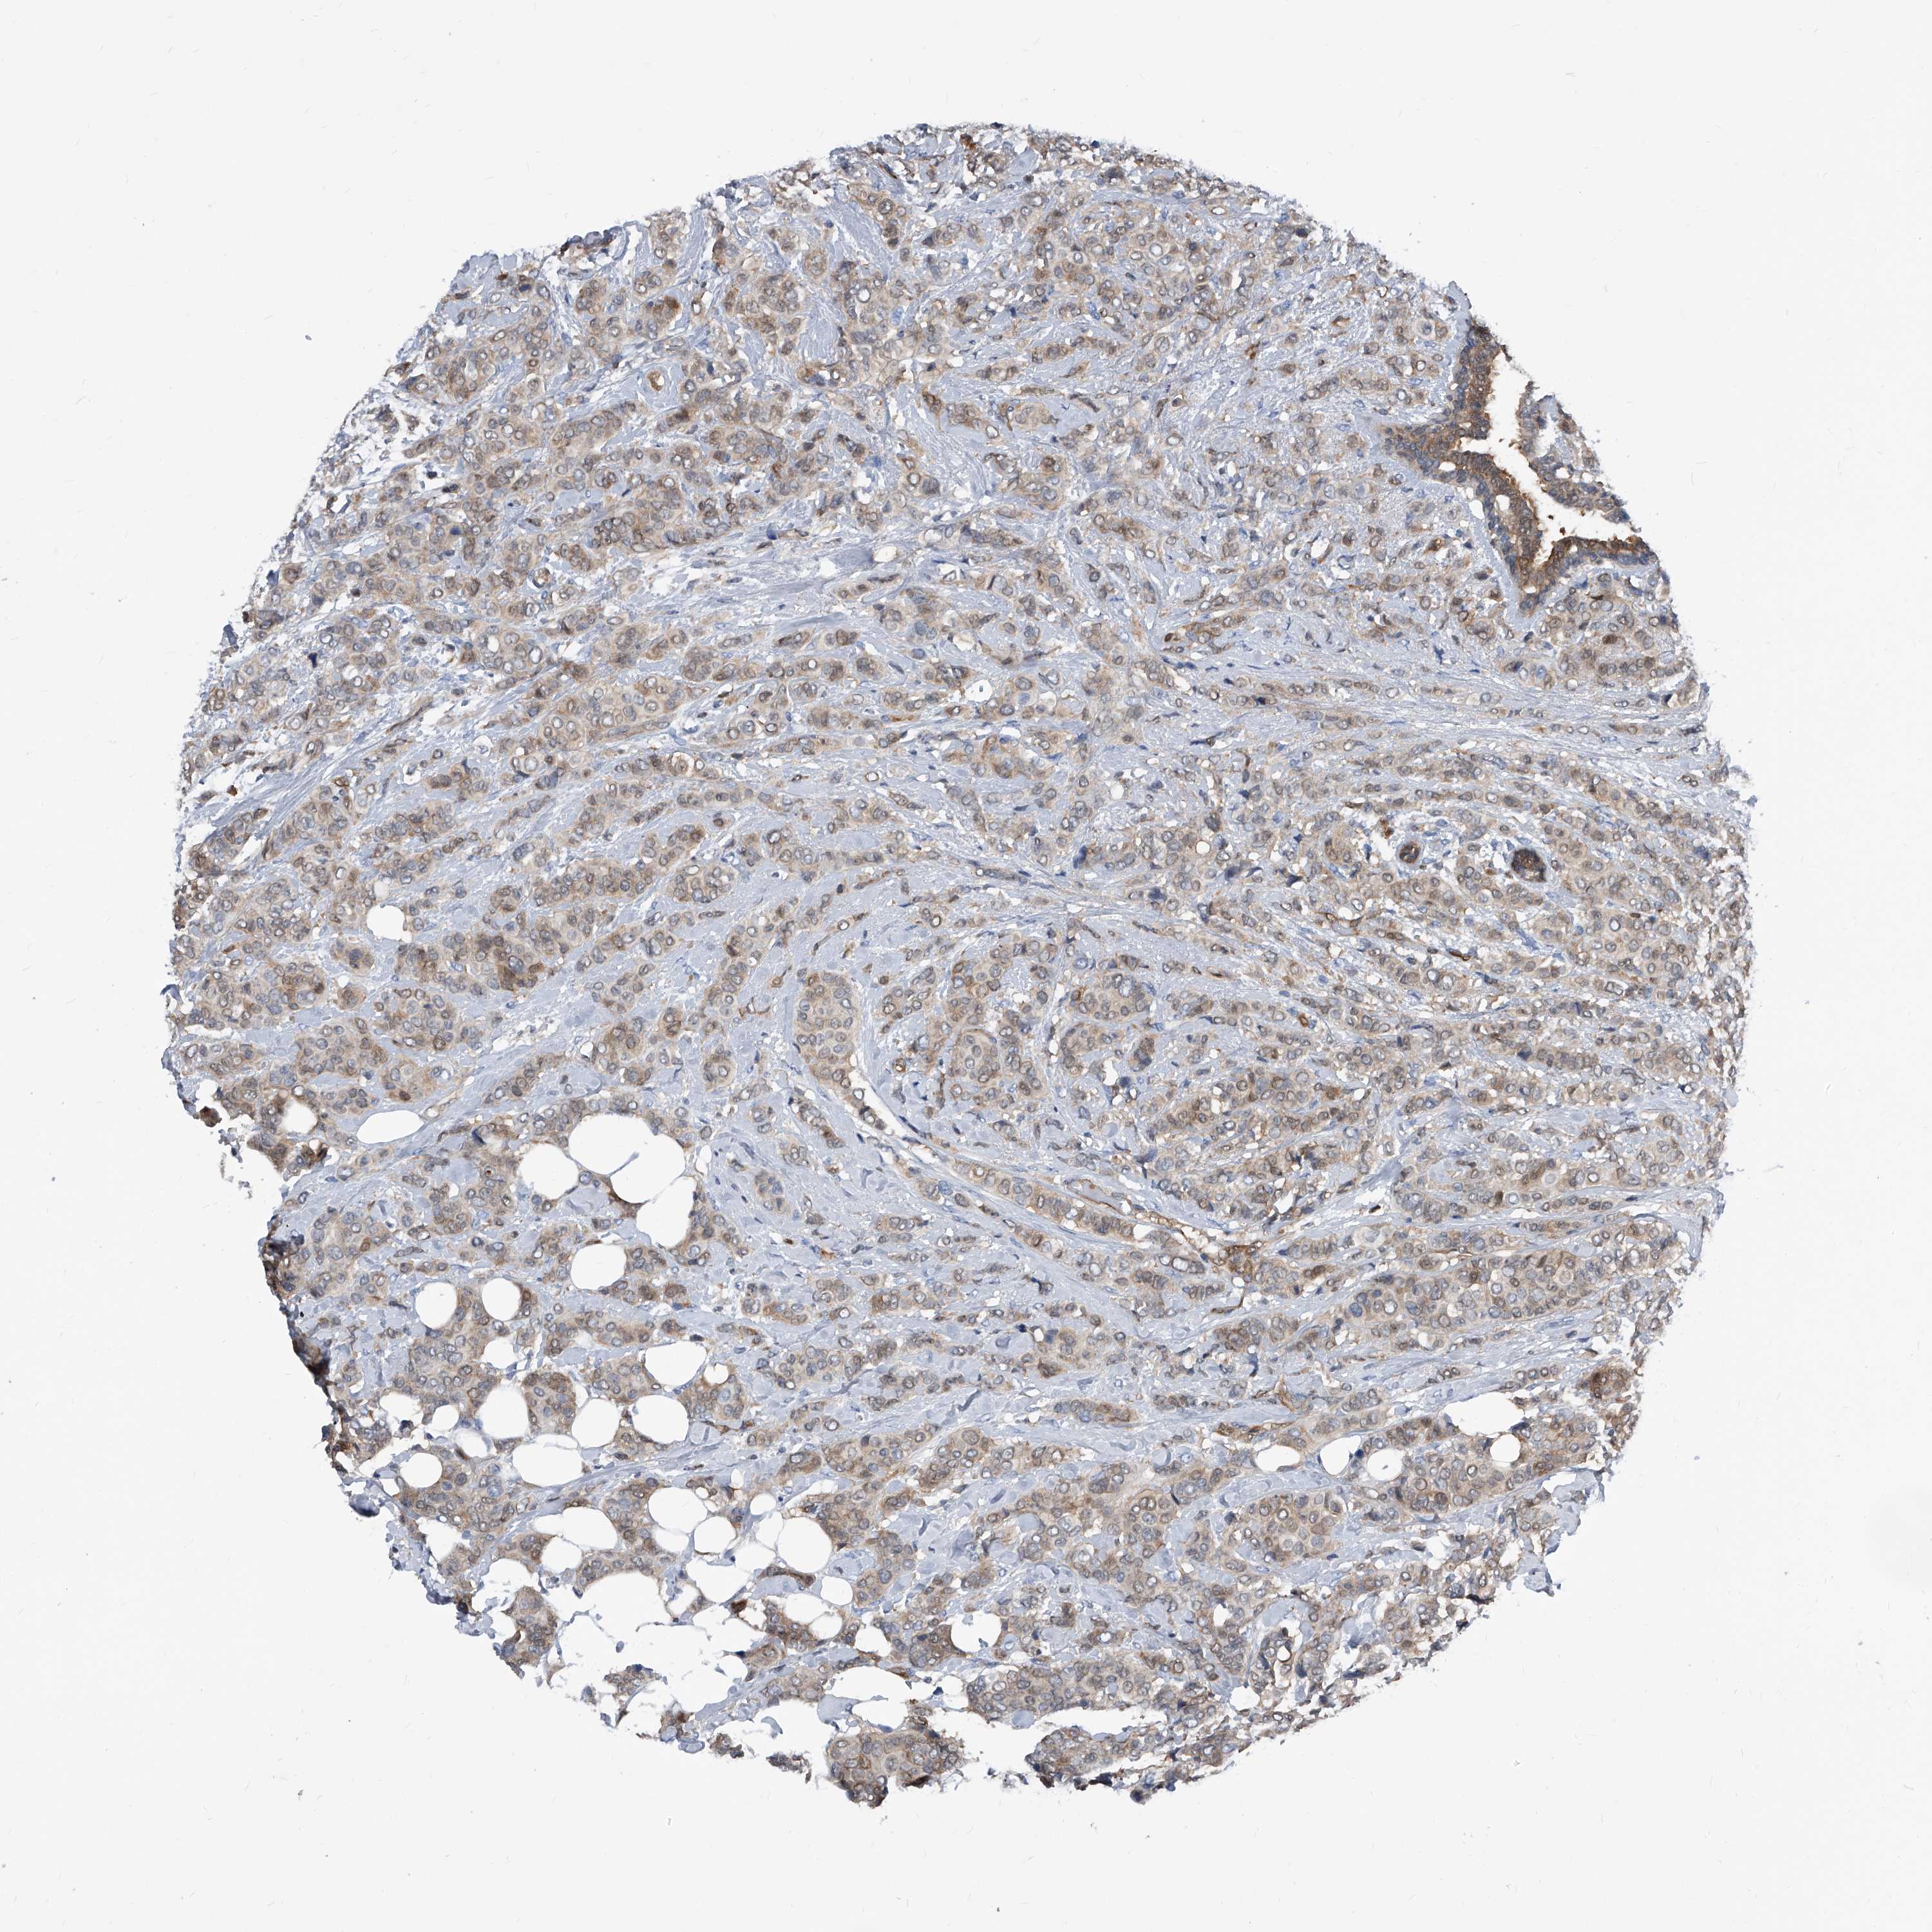

CANCER BREAST CANCER Show tissue menu

BRCA TCGA BRCA VALIDATION PROTEIN EXPRESSION